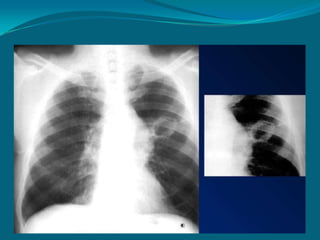

DERRAMES

PLEURALES/HIDROTÓRAX

 Trasudado, exudado,

sangre, quilo, etc; que se

presenta como una

densidad bien definida en

el espacio pleural

El angulo

costofrenico

derecho esta

obliterado por un

derrame pleural

secundario a

fallo cardiaco

(existe

cardiomegalia).